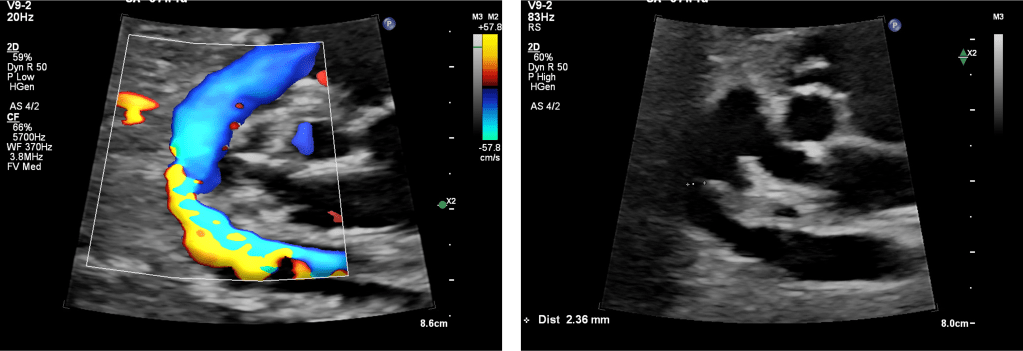

Detection relies on Doppler assessment of ductal flow and evaluation of the fetal right heart. Key elements include ductal peak systolic velocity (PSV), pulsatility, diastolic flow, and secondary RV changes.

4. Functional Severity Assessment

Severity is defined by functional consequences rather than velocity alone.

• Mild: Preserved pulsatility, forward systolic and diastolic flow, normal RV size and function.

• Moderate: Reduced pulsatility, shortened diastolic flow, mild RV hypertrophy or tricuspid regurgitation (TR).

• Severe: Minimal or absent diastolic flow, non‑pulsatile waveform, RV dilatation or dysfunction, moderate–severe TR.

5. Ductal Arch View: Practical Imaging Recommendations

• Use a longitudinal ductal arch view of the fetus.

• Ensure near‑parallel insonation.

• Avoid oblique sampling from the three‑vessel trachea view alone.

• Assess flow pattern, not velocity alone.